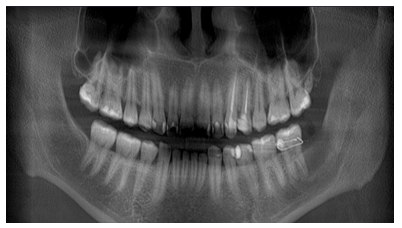

Se apreció en la ortopantomografía imagen pseudo radiolúcida localizada en el límite posterior del cuerpo mandibular, que se extendía desde las raíces de UD 37 hasta tercio medio de rama mandibular ipsilateral de bordes definidos, desplazando el conducto alveolar inferior y sin afectar la basal mandibular.

Figura 2 Detalle de Radiografía Panorámica que evidencia imagen pseudo radiolúcida unilocular de bordes corticalizados que se extiende en sentido cefálico caudal desde borde anterior de la rama y parte del reborde alveolar hasta la cortical del conducto mandibular izquierdo, se evidencia relación de la lesión con raíces de la UD 37. Fuente: Historia Clínica. Especialización Cirugía Bucal ULAC-IDOLA. 2022.